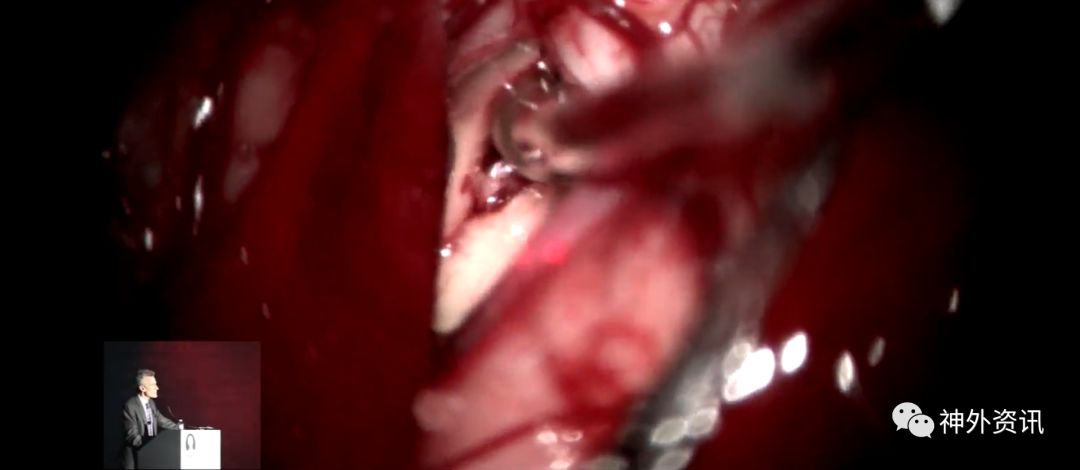

Michael T. Lawton,巴洛神经科学研究所(BNI)主席,精于各种脑血管疾病的治疗,已累及外科治疗4400余例颅内动脉瘤和700余例AVM,发表论文270余篇,参编书籍40余部,著有《Seven Aneurysms: Tenets and Techniques for Clipping》。